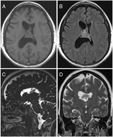

Our patient was a 60-year-old female who initially presented with intractable headaches, anosmia, and forgetfulness. Neurological examination revealed no focal neurological deficits, and the patient was otherwise healthy. Computed tomography (CT) and magnetic resonance imaging (MRI) of the head revealed a 2.8 × 3.0 × 2.7 cm mixed cystic and solid mass attached to the septum pellucidum extending into both lateral ventricles, with obstruction of the foramen of Monro (Figure 1).

Figure 1: Preoperative MRI showed an intraventricular mass. (A) Axial T1-weighted image, (B) Axial T2-weighted FLAIR image, (C) Sagittal CISS image and (D) Coronal T2-weighted image demonstrating a mixed cystic and solid mass centred on the septum pellucidum with extension into bilateral lateral ventricles (right greater than left). FLAIR – Fluid Attenuation Inversion Recovery, CISS – Constructive Interference Steady State.